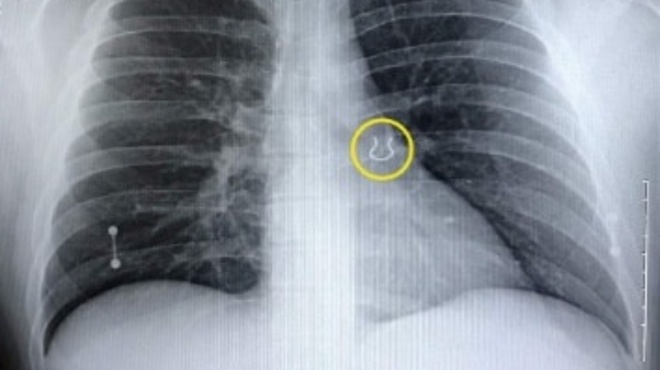

Την επόμενη μέρα πήγε στο νοσοκομείο για εξετάσεις και η ακτινογραφία αποκάλυψε κάτι ασυνήθιστο στον άνω λοβό του αριστερού πνεύμονα. Ο γιατρός του έδειξε τη σάρωση και το μικρό, αντικείμενο τον άφησε άναυδο.

Ήταν το σκουλαρίκι μύτης που είχε χάσει πριν από χρόνια και που ποτέ δεν θα περίμενε να βρει στον πνεύμονά του

«Ο γιατρός ήρθε και μου έδειξε την εικόνα της ακτινογραφίας και μου είπε: Σας φαίνεται γνωστό αυτό;». θυμήθηκε ο Joey Lykins. «Έλεγα: Πλάκα μου κάνετε! Το έψαχνα αυτό. Δεν ήξερα τι συνέβαινε, αλλά ποτέ δεν θα πίστευα ότι ήταν αυτό».